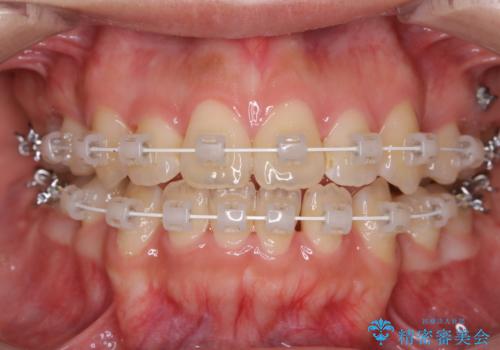

- 定期的にメンテナンスにいらしている方です。特にお変わりないとのことでPMTC60分コースで全体的なクリーニングを行いました。